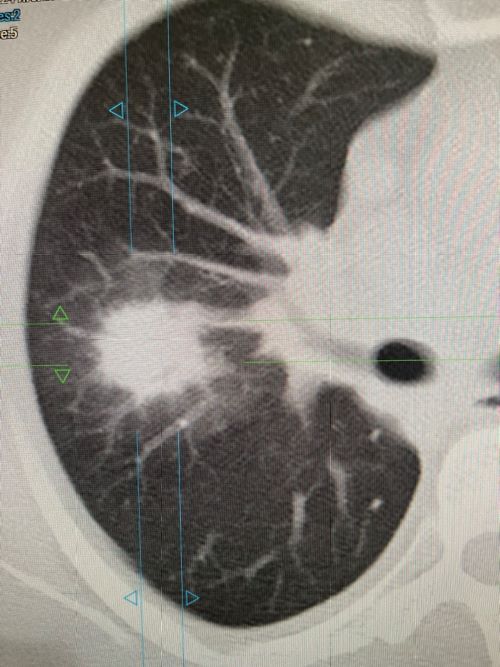

После проведённого сканирования были выявлены поражения в обоих лёгких, с выраженным инфильтратом в верхней доли правого лёгкого.

После интерпретации полученных снимков пациентке выставлен диагноз: Двустроронняя полисегментарная пневмония. Лимфоаденопатия ВГЛУ. Образование ? в верхней доле правого лёгкого.

По окончании лечения рекомендовано контрольное обследование на МСКТ для исключения новообразования.